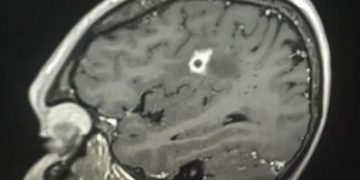

Medicos han descubierto moho negro toxico creciendo en el cerebro de un hombre de Estados Unidos. El hongo Cladophialophora bantiana … Sigue leyendo Medicos descubren moho negro creciendo en el cerebro de un hombre